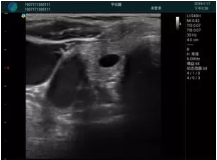

清晰顯示孕囊,通過軟件包計(jì)算孕齡7w+6d

M20實(shí)時(shí)引導(dǎo),術(shù)中清晰顯示孕囊被破壞和抽吸針的過程,清晰顯示吸引針

抽吸結(jié)束后縱切子宮,孕囊已被完全抽吸,未見明顯殘留

橫切子宮,發(fā)現(xiàn)右側(cè)宮腔靠近宮角處有少許脫模樣殘留

M20引導(dǎo)下,抽吸針找到右側(cè)宮角處再次清掃

二次抽吸后再次進(jìn)行超聲檢查,宮腔未見殘留,宮腔線清晰顯示